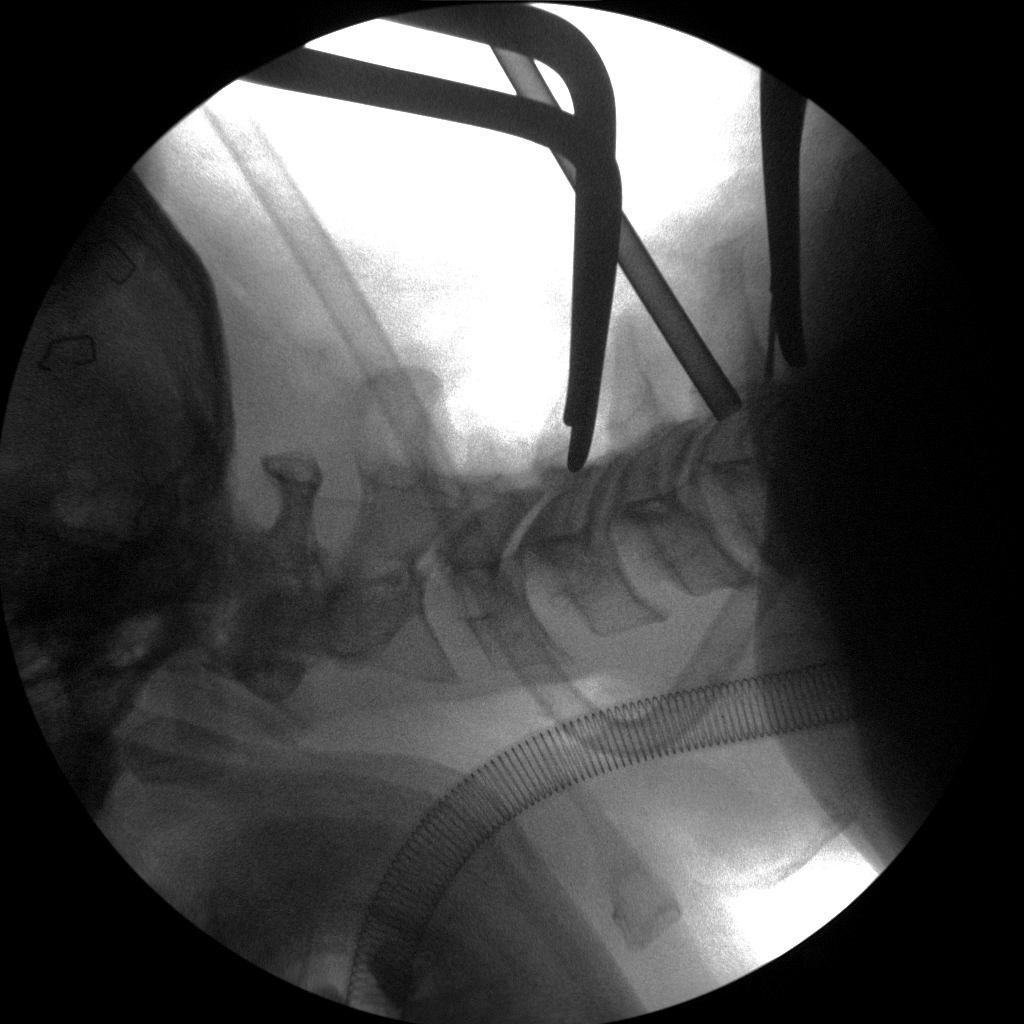

High-quality imaging

Skan-C uses advanced imaging technology, such as pulsed fluoroscopy and digital subtraction angiography, to provide highly detailed images of the affected area. This allows doctors to perform procedures with increased precision and accuracy, and better patient outcome

Clinical Evidence

Skan-C is a great C-arm for neurology treatments for several reasons